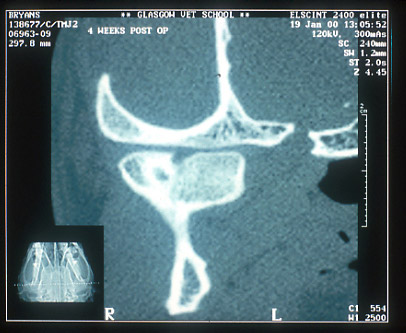

CT scan of same fractured mandibular condyle 4 weeks post-trauma